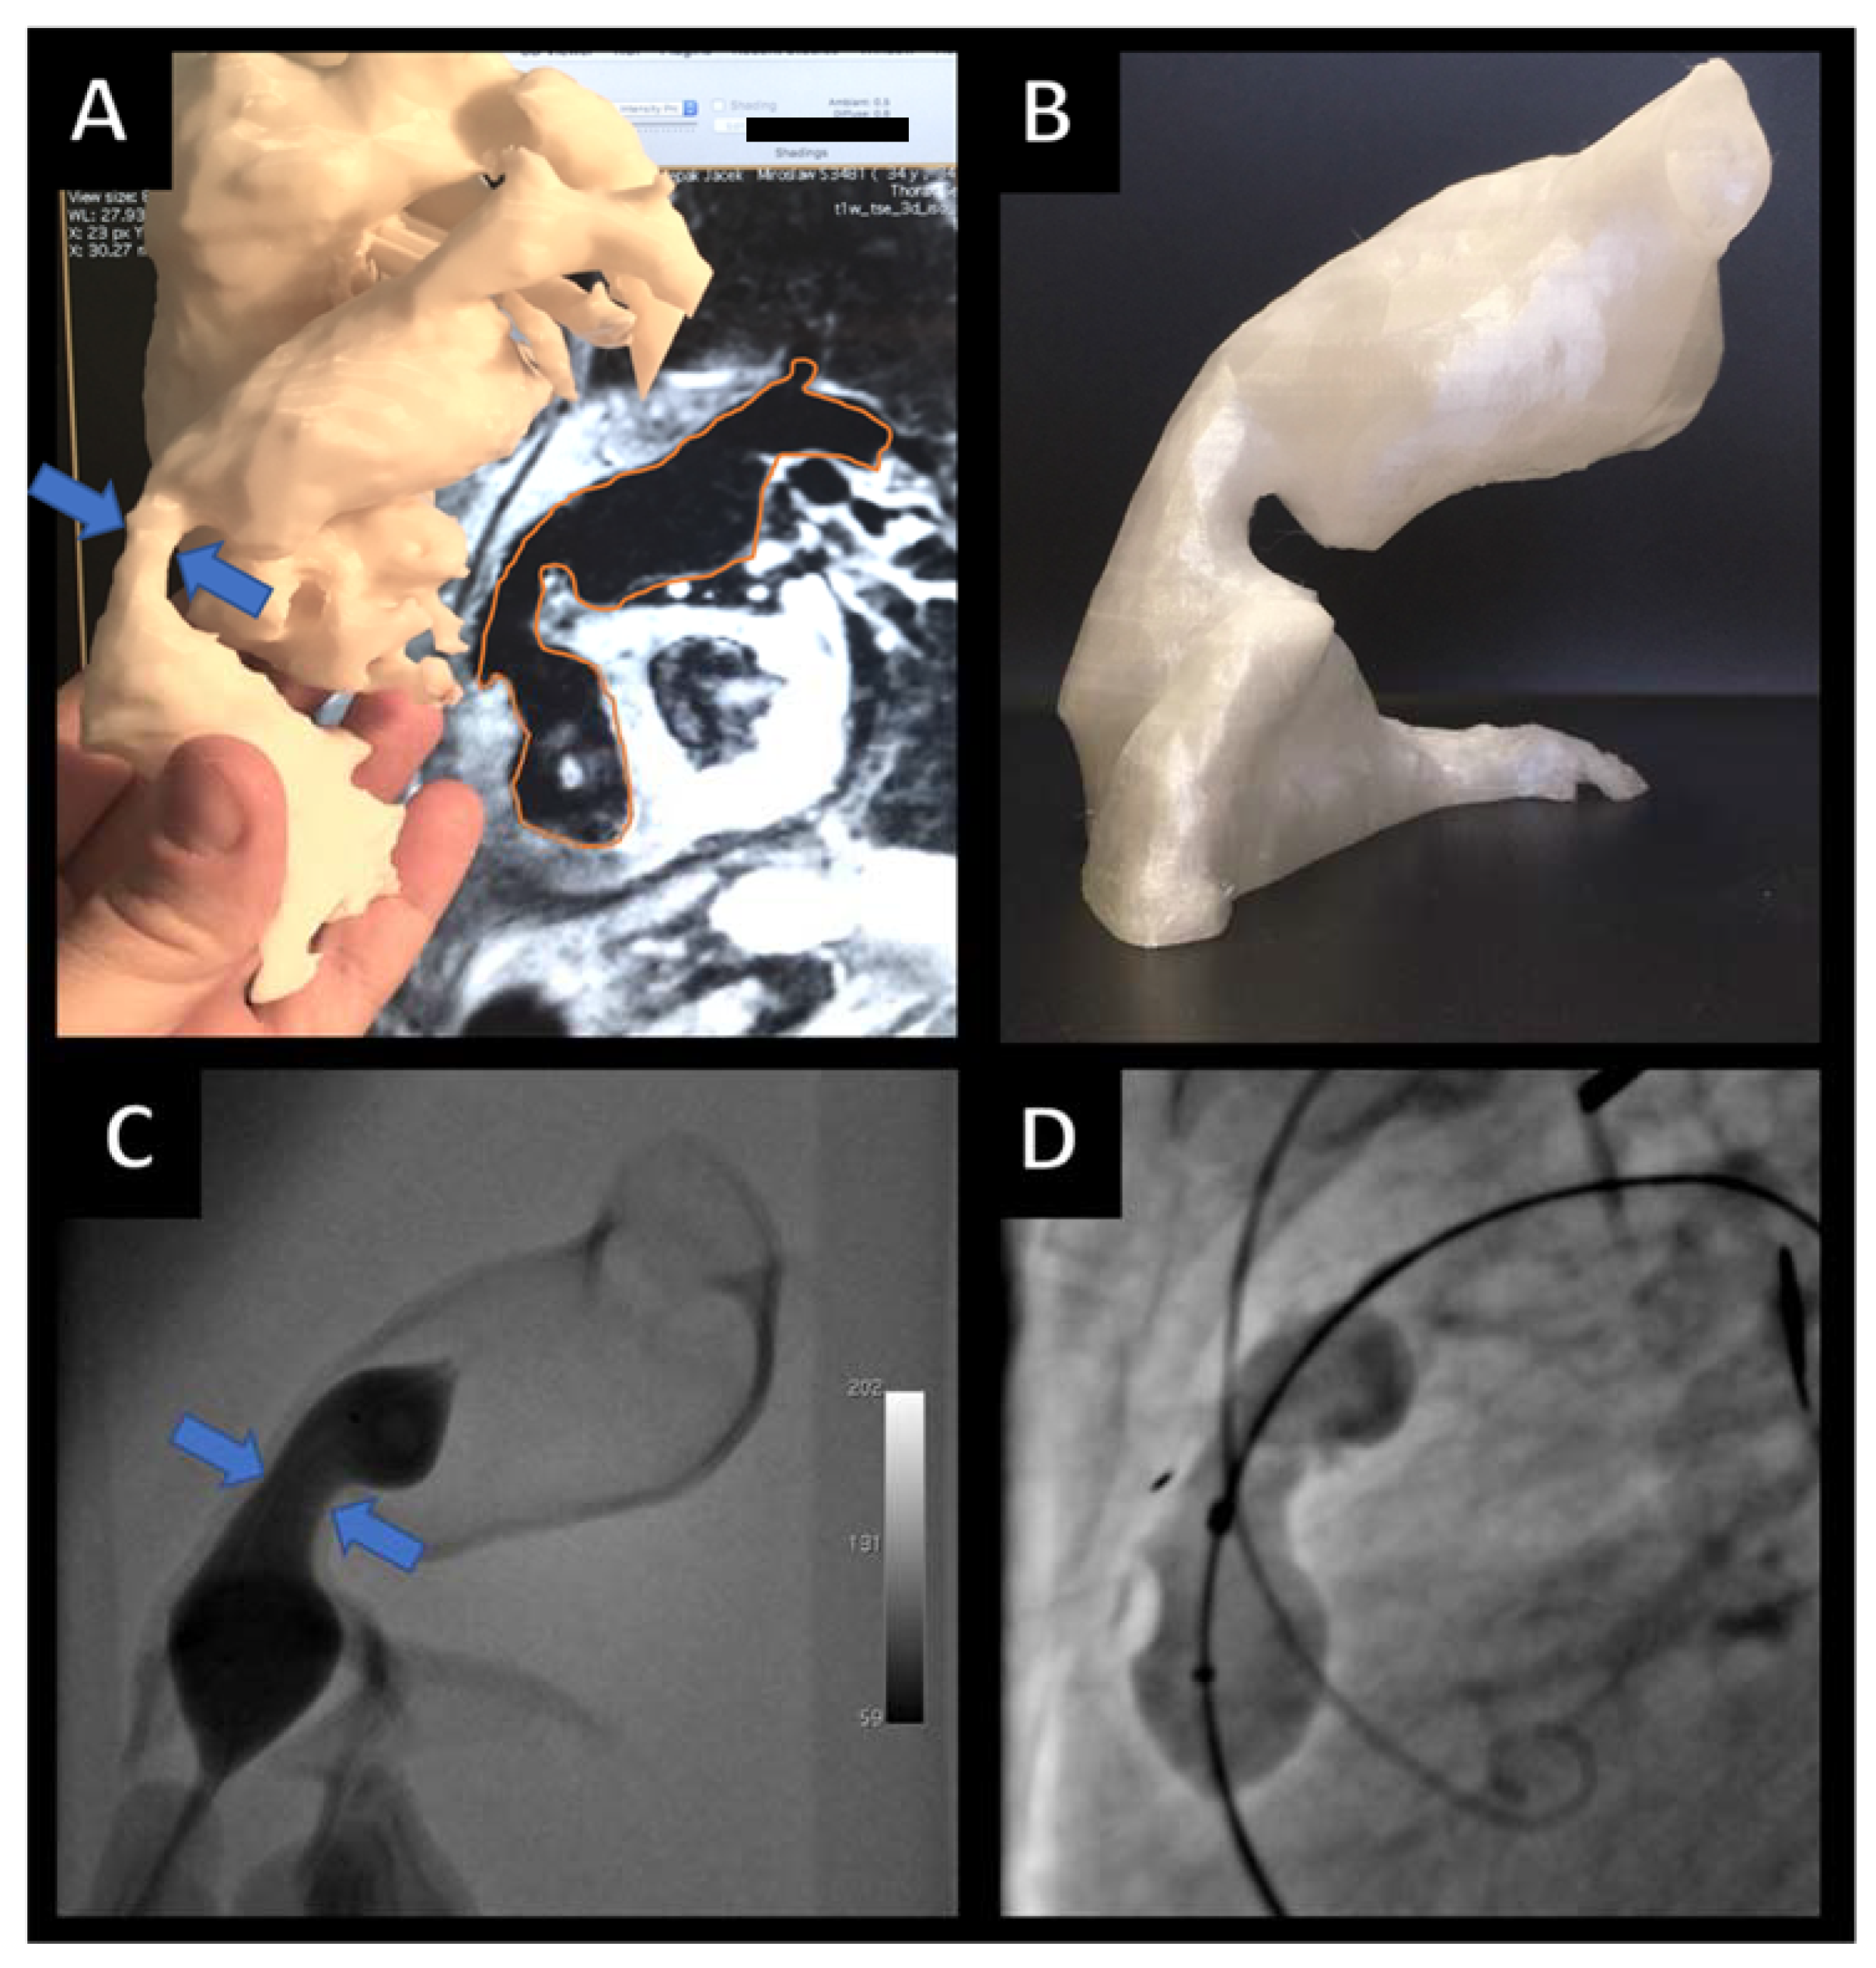

- Sabiniewicz, R.; Meyer-Szary, J.; Potaż, P.; Jagielak, D.; Moszura, T. Melody Valve Implantation Pre-Procedural Planning Using Custom-Made 3D Printed Model of the Region of Interest. Adv. Interv. Cardiol. 2018, 14, 210–211. [Google Scholar] [CrossRef] [PubMed]

- Sabiniewicz, R.; Meyer-Szary, J.; Woźniak-Mielczarek, L.; Sabiniewicz, D. Follow-up on Results of Three-Dimensional Printed Model Aided Unusual Intervention on Aneurysm of Aortic Arch Lesser Curvature. Cardiol. J. 2020, 27, 447–448. [Google Scholar] [CrossRef] [PubMed]